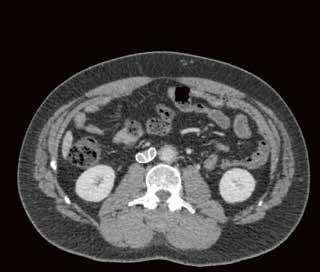

Fall 1:

Biphasische Abdomen-CT bei einer deutlich adipösen Patientin. Hier lässt sich sowohl Dosis sparen als auch die Qualität der Rekonstruktionen verbessern. Beispielsweise findet sich deutlich weniger Bildrauschen, insbesondere im Bereich der parenchymatösen

Portalvenöse Abdomen-CT. Auch hier ist die Dosis am Aquilion Prime SP mit AiCE geringer, zudem auch hier geringeres Bildrauschen mit sehr guter Abgrenzbarkeit, beispielsweise von Leberläsionen.

Abb. 1 a: biphasische Abdomen-CT, Canon Aquilion Prime, Rekonstruktion: AIDR 3D; DLP 1003,6 mGy × cm / 18,1 mSv. Abb. 2 a: biphasische Abdomen-CT, Canon Aquilion Prime, Rekonstruktion: AIDR 3D; DLP 1003,6 mGy × cm / 18,1 mSv. Abb. 1 b: biphasische Abdomen-CT, Canon Aquilion Prime, Rekonstruktion: AiCE; DLP 716,5 mGy × cm / 12,9 mSv. Abb. 2 b: biphasische Abdomen-CT, Canon Aquilion Prime, Rekonstruktion: AiCE; DLP 716,5 mGy × cm / 12,9 mSv. Oberbauchorgane.